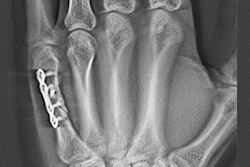

Images are of a 67-year-old man with rheumatoid arthritis. Bone erosion with significant overlapping of bones (arrows) can be difficult to evaluate on radiography (above), compared with tomosynthesis (below and bottom). Images courtesy of AJR.